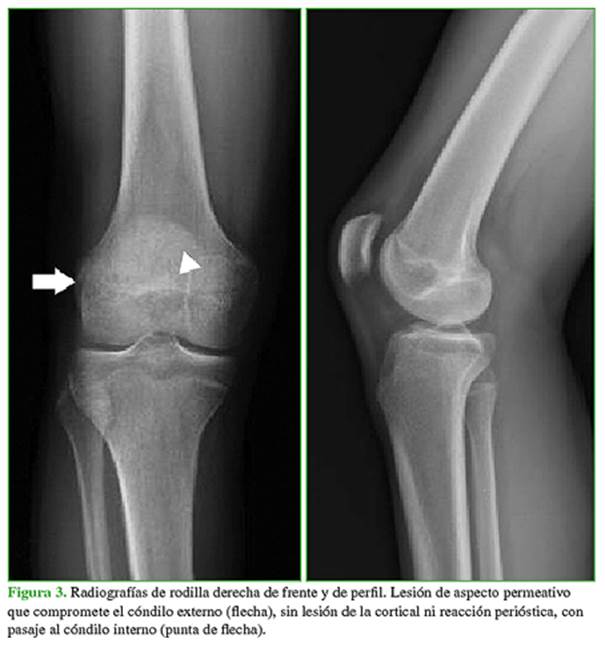

En la radiografía, se identifica un patrón permeativo, con marcado compromiso del cóndilo externo y, en menor medida, del cóndilo interno (Figura 3).